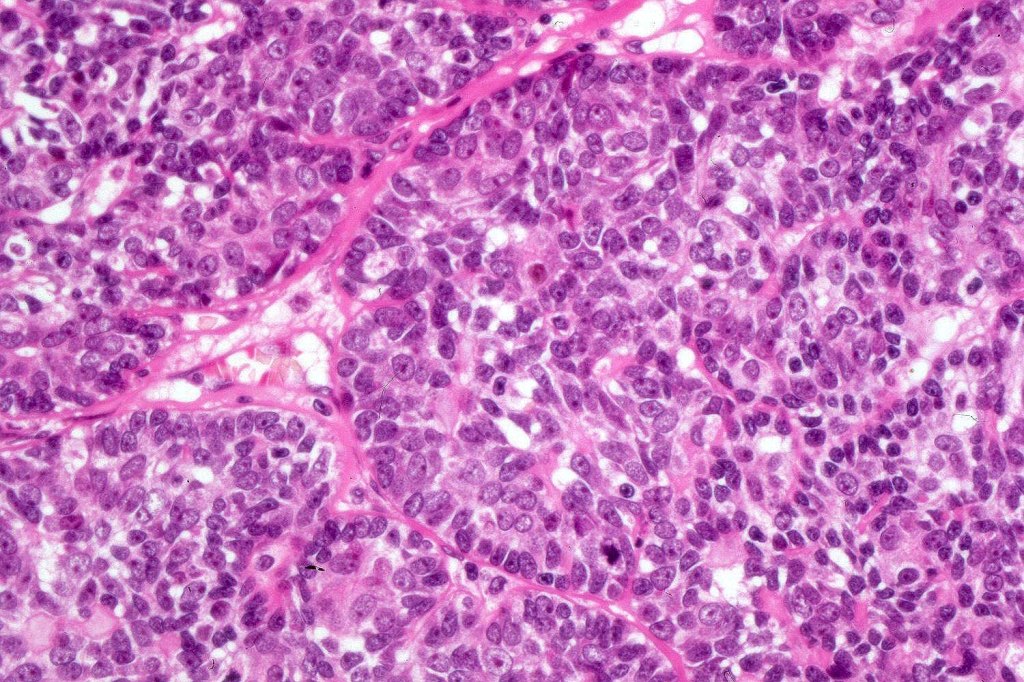

Histological features

•Pre-existent spiradenoma

•Malignant component shows loss of dual cell population, increased mitotic activity, atypical mitoses & necrosis

•Perineural infiltration & LVI may be present